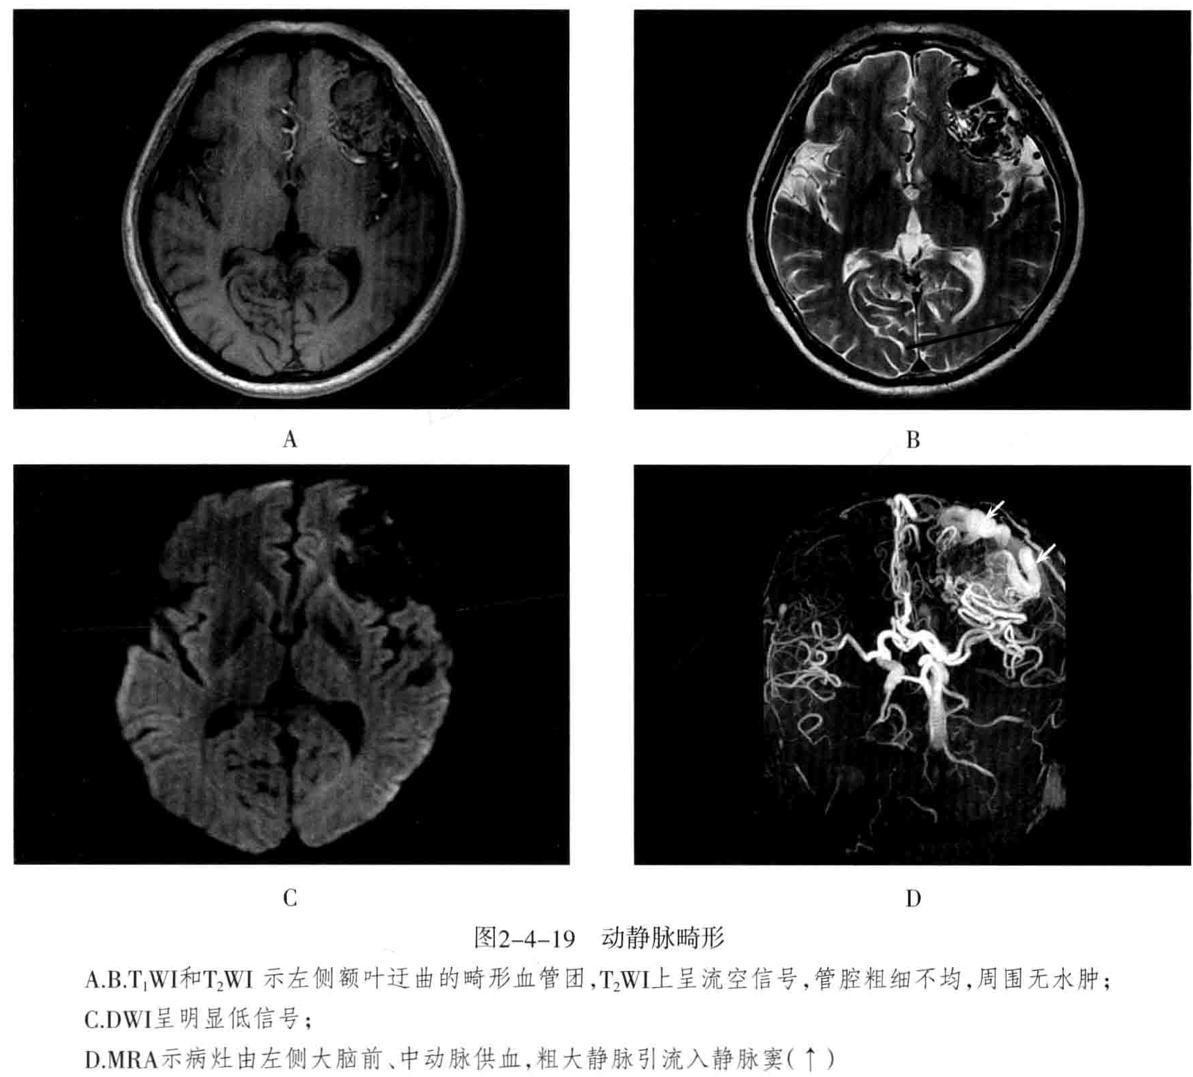

- 动静脉畸形(AVM ): 迂曲扩张的 供血动 脉与 引流静脉 之间无正常毛细血管,而是通过 畸形的血管 袢 直接相通,形成 异常的血管团 。畸形血管易破裂出血,由于动静脉短路,周围脑组织因缺血而发生萎缩,称为“盗血”现象。多见于大脑中动脉分布的脑皮质,也可发生于侧脑室脉络丛、硬脑膜、软脑膜、小脑及脑干。主要临表:出血(蛛网膜下腔出血及脑实质出血)、癫痫、头痛。

- 脑血管造影(DSA)及CTA :是诊断AVM的可靠办法,可以显示动静脉畸形血管团、明显增粗迂曲的供血动脉及引流静脉。

- CT检查:平扫表现为局灶性团块状或点状混杂密度区、形态不规则,边界不清,可见钙化;增强扫描病灶区呈蚯蚓状、团块状强化,有时可见点线状迂曲的扩张血管影,其周围可见粗大的供血动脉及迂曲扩张的引流静脉。可出现局限性脑萎缩,无占位效应、无脑水肿。

- MRI检查:畸形血管团由于流空效应,在T1WI及T2WI上均无信号,供血动脉表现为低或无信号。不伴有出血时,病灶无占位效应及周围水肿,邻近脑组织呈萎缩。